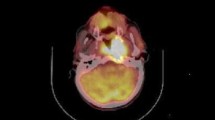

All patients were fasted for at least 8 h prior to 18F-FDG PET/CT scanning, and their blood glucose level was measured. All patients were rested for at least 1 h before PET/CT scan. 18F-FDG (5.55–7.40 MBq/kg), of radiopharmaceutical purity >95%, was injected intravenously. After 1 h, images were acquired in 2D mode on a Discovery LS PET/CT, GE. The maximal standard uptake value (SUVmax) in each region of interest (ROI) was determined using the whole-body attenuation corrected image and the formula, tissue concentration of 18F-FDG measured by PET/the injected dose/body weight. All the 41 patients underwent the pre- and post-treatment whole-body 18F-FDG PET/CT scan as part of routine follow-up of 2–3 months after treatment completion (Greven et al. 2001).

The ability of MTV and MI to predict prognosis were depicted by ROC curve. Areas under the curve (AUC) are 0.759 and 0.779, respectively. Figure 1 shows the ROC curve of MI. And the best cutoff values are 30 and 130 cm3, respectively. Patients having tumors with an MTV below 30 cm3 had significantly better 5-year OS (84.6:46.7%, P = 0.006) and DFS (73.1:40.0%, P = 0.014) than patients with an MTV of 30 cm3 or greater. And the patients with MI below 130 had significantly higher 5-year OS (88.0:43.8%, P = 0.002) and DFS (76.0:37.5%, P = 0.005) than other patients, as shown in Figs. 2 and 3.

Fig. 1 Fig. 2 -